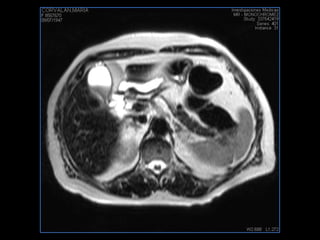

PROTOCOLO abdomen COR T2, AXIAL supresion grasa AX T1 +SAG T2  CON   GADOLINIO :  COR T1+AX T1(DIN) SAT: NO  FASE: RL THK: 6MM  COIL:  GAP: (FACTOR 1.4) 2MM FOV: 40 CM NEX:2 SINCRONIZACION RESPIRATORIA EN 3 O 4 CICLOS ALE